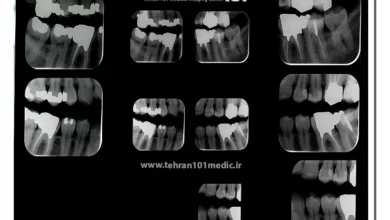

انواع رادیوگرافی دندان

رادیولوژی دندان از تصاویر رادیوگرافی برای بررسی جزئیات دقیق دندانها، ریشهها و ساختارهای جمجمه استفاده میکند. این تصاویر به دندانپزشکان…

تفسیر عکس رادیوگرافی دندان

عکس رادیوگرافی دندان بر روی فیلم ظاهر میشود که در آن چیزی جز سفیدی و سیاهی دیده نمیشود. رادیوگرافی راهی…